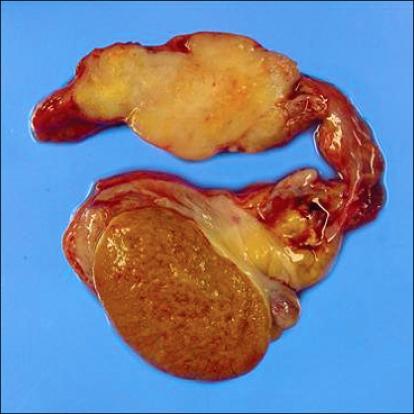

Malignant mesothelioma of the spermatic cord.

Primary tumors arising from the spermatic cord are very rare. Mesothelioma derives from the mesothelial cells lining the serous membrane, such as the pleura, peritoneum, and tunica vaginalis of testis. Paratesticular malignant mesothelioma (MM), which usually presents as a hydrocele or intrascrotal mass, accounts for 0.3% to 1.4% of MMs. MMs of the spermatic cord account for less than 10% of paratesticular MMs. We report a case of MM of the spermatic cord in a 65-year-old man who primarily presented to the hospital with a left inguinal mass. Following the diagnosis after surgery, he was found to have a contralateral right inguinal mass and died in 6 months. Despite their rare occurrence in the spermatic cord, MMs need to be suspected, especially in patients with a history of asbestos exposure.